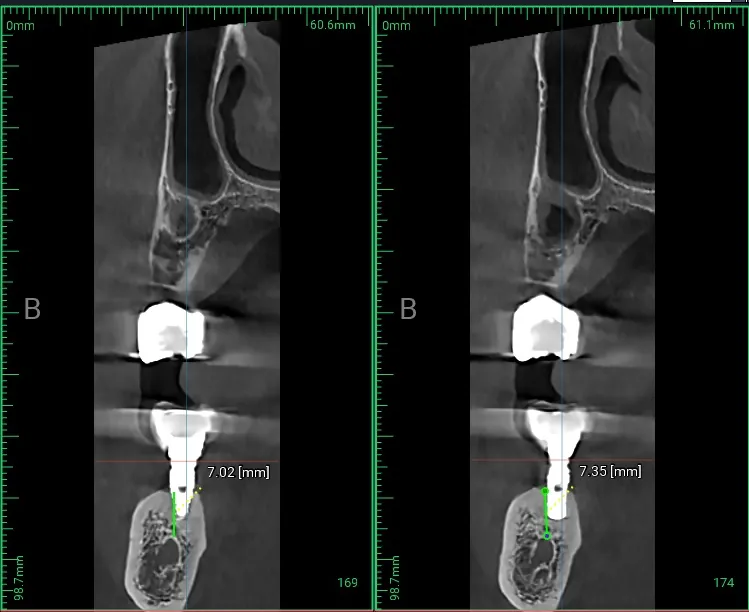

CBCT 3D 스캔 — 신경관 상방으로 7.02mm, 7.35mm의 제한적 골 높이 확인

염증으로 인해 뼈가 녹으면, 새로 심을 임플란트를 지지해 줄 뼈(상방 골, Available Bone Height)가 부족해집니다.

통상 어금니에 쓰기 위한 임플란트는 8.5mm 길이 정도 되는 것이 좋은데, 3차원 사진(CBCT, Cone Beam Computed Tomography)을 통해 확인해 보면 신경관(Inferior Alveolar Nerve Canal) 상방으로 약 7mm밖에 없는 것을 볼 수 있습니다.

이런 경우 짧은 임플란트(Short Implant)를 신경관을 다치지 않게 아주 정밀하게 식립해야 합니다!

- 잔존 골 부족 — 신경관 상방에 7mm밖에 남지 않아 짧은 임플란트를 정밀 식립해야 함